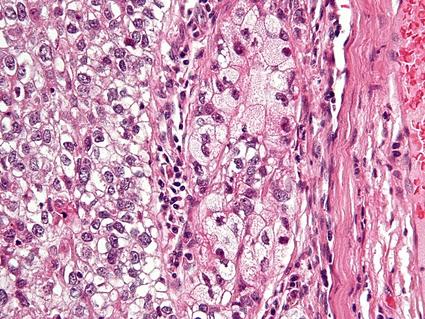

This is the first paper to provide evidence-based, multidisciplinary guidance for the diagnostic evaluation and surgical management of pediatric cutaneous melanoma. The recommendations also address diagnosis and management of atypical Spitz and non-Spitz melanocytic tumors in pediatric patients.

Diagnosis of these malignancies in pediatric patients is challenging because benign and malignant melanocytic tumors may exhibit similar clinicopathologic features in this age group. The guidelines seek to address diagnostic ambiguity, improve tumor classification through the use of next generation sequencing, and minimize treatment variability.